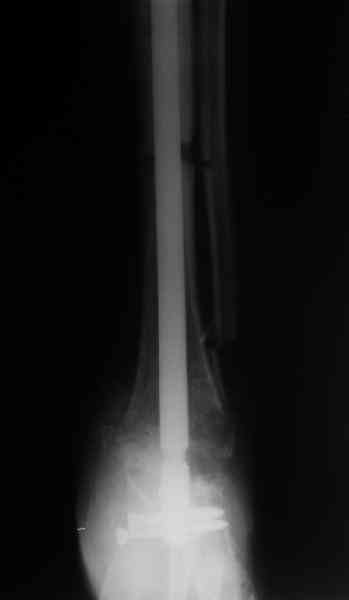

Аппарат был снят окончательно только после введения стержня, то есть оставалось по одной спице в проксимальном и дистальном метафизах большеберцовой кости, спицы в пятке. Фото во время рассверливания в приложении.

Стержень 12 мм, винт диаметром 6 мм, костная трубка вокруг хорошая. Перелом такого винта пока не наблюдали ни разу на нескольких сотнях

пациентов.